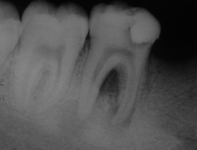

Дополнительно: Наиболее частая причина возникновения кариеса – неудовлетворительная гигиена полости рта. Методика лечения выбирается исходя из клинической ситуации после рентгенографического исследования

При глубоком кариесе патологический процесс распространяется глубоко и доходит до околопульпарного дентина. Между пульпой и дном кариозной полости может остаться очень тонкий слой здорового дентина. Лечение кариеса в этом случае рекомендуется проводить в два этапа и вот почему. Кариесогенные бактерии могли проникнуть через здоровый дентин в пульпу и вызвать воспаление. Чтобы удостовериться, что этого не произошло, после удаления кариозных тканей ставят лекарственную прокладку, затем – изолирующую, и закрывают полость временной пломбой. Если через 3-4 дня в герметично закрытом зубе не возникло болевых ощущений, значит, воспаления нет и можно ставить постоянную пломбу.

При глубоком кариесе, осложненном пульпитом или периодонтитом, проводят эндодонтическое лечение – выполняют депульпирование (удаляют нерв). После депульпирования при пульпите пломбируют корневые каналы, при периодонтите проводят лечение, направленное на ликвидацию воспаления на верхушке корня, и только потом пломбируют каналы. После пломбировки каналов устанавливают пломбу.